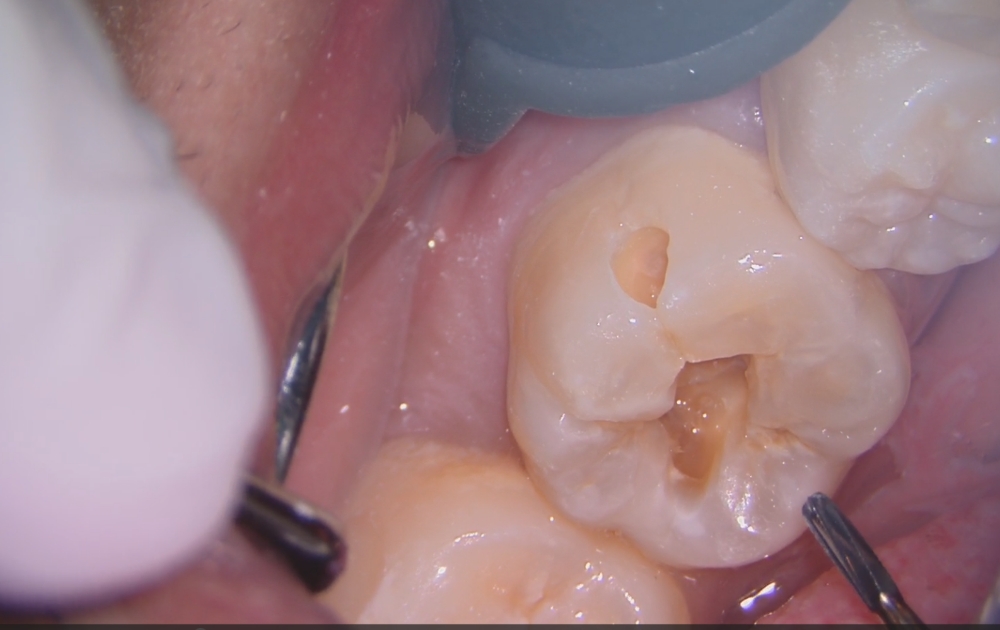

• 1.削る前の最初の状態です。表面にはごく小さな穴が開いているだけですが、この段階では内部の広がりは外から判断できません。

• 2.外側を少しずつ削ることで、内側に広く虫歯が進行していることが分かります。見た目以上に深いケースも多く、慎重な確認が必要です。

1.削る前の最初の状態です。

表面にはごく小さな穴が開いているだけですが、この段階では内部の広がりは外から判断できません。

2.外側を少しずつ削ることで、内側に広く虫歯が進行していることが分かります。

見た目以上に深いケースも多く、慎重な確認が必要です。